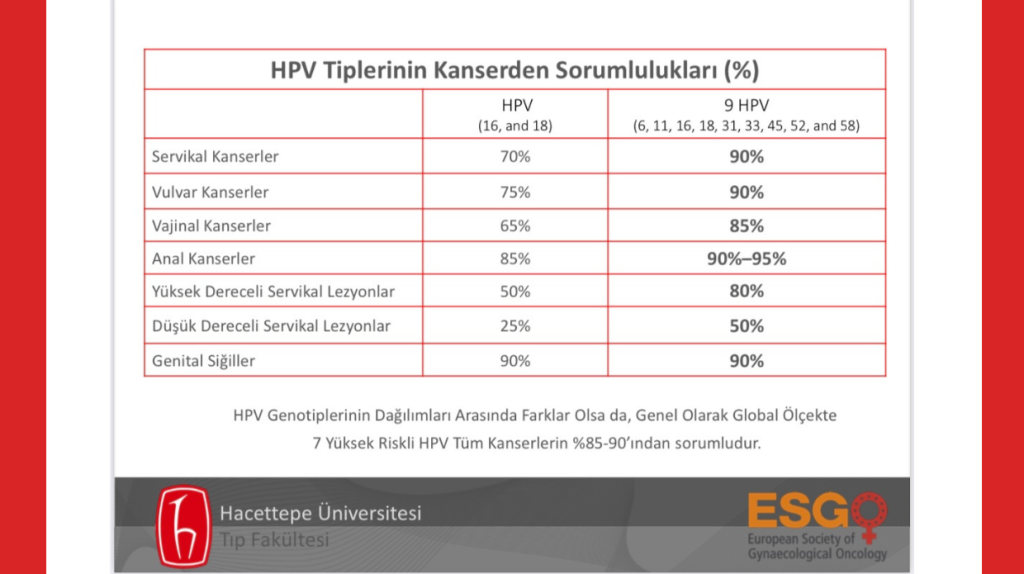

HPV, 200’ün üzerinde tipi olup, bunlardan 40 kadarı genital bölge hedefli olan bir virüs. Kanserle bağı bilinen en yüksek unsur. Dünyadaki tüm kanserlerin %5’ine, dünyadaki tüm kadın kanserlerinin %10’una kaynaklık ediyor. Bazı tipleri (Tip 6 ve Tip 11) genital siğillere neden oluyorken bazı tipleri de (sadece Tip 16 ve Tip 18 Rahim ağzı kanserinin %70’inden sorumlu) kansere ve öncülü rahatsızlıklara yol açmakta. Ağırlıklı oranda cinsel yolla bulaşan bu virüs aşısız toplumlarda maalesef çok yaygın. Kadınların %80’inin yaşamı boyunca en az bir HPV enfeksiyonu geçirdiği biliniyor. Erkeklerin durumu da daha iyi değil. Bir kadının ilk cinsel deneyiminde HPV enfeksiyonu geçirmesinin kümülatif riski %46, yani yaklaşık 2 kişiden biri. Kayıtlı rakamlara göre (ki aslında gerçek sayılar çok daha fazla) dünyada yılda yaklaşık 600 bin kadın HPV’ye bağlı kanser olmakta ve bunların 350 bin kadarı yaşamını yitirmekte. Erkekler ise bilinenin aksine sadece taşıyıcı değil; kadınlardaki kadar marjinal rakamlarda olmasa da yılda yaklaşık 40 bin erkek de HPV’ye bağlı kansere yakalanır durumda. Bunlar çok üzücü sayısal bilgiler. Ama bundan kurtulmanın bir yolu var: “Çocuk yaşta ulusal aşı takvimi kapsamında aşılanmak.”